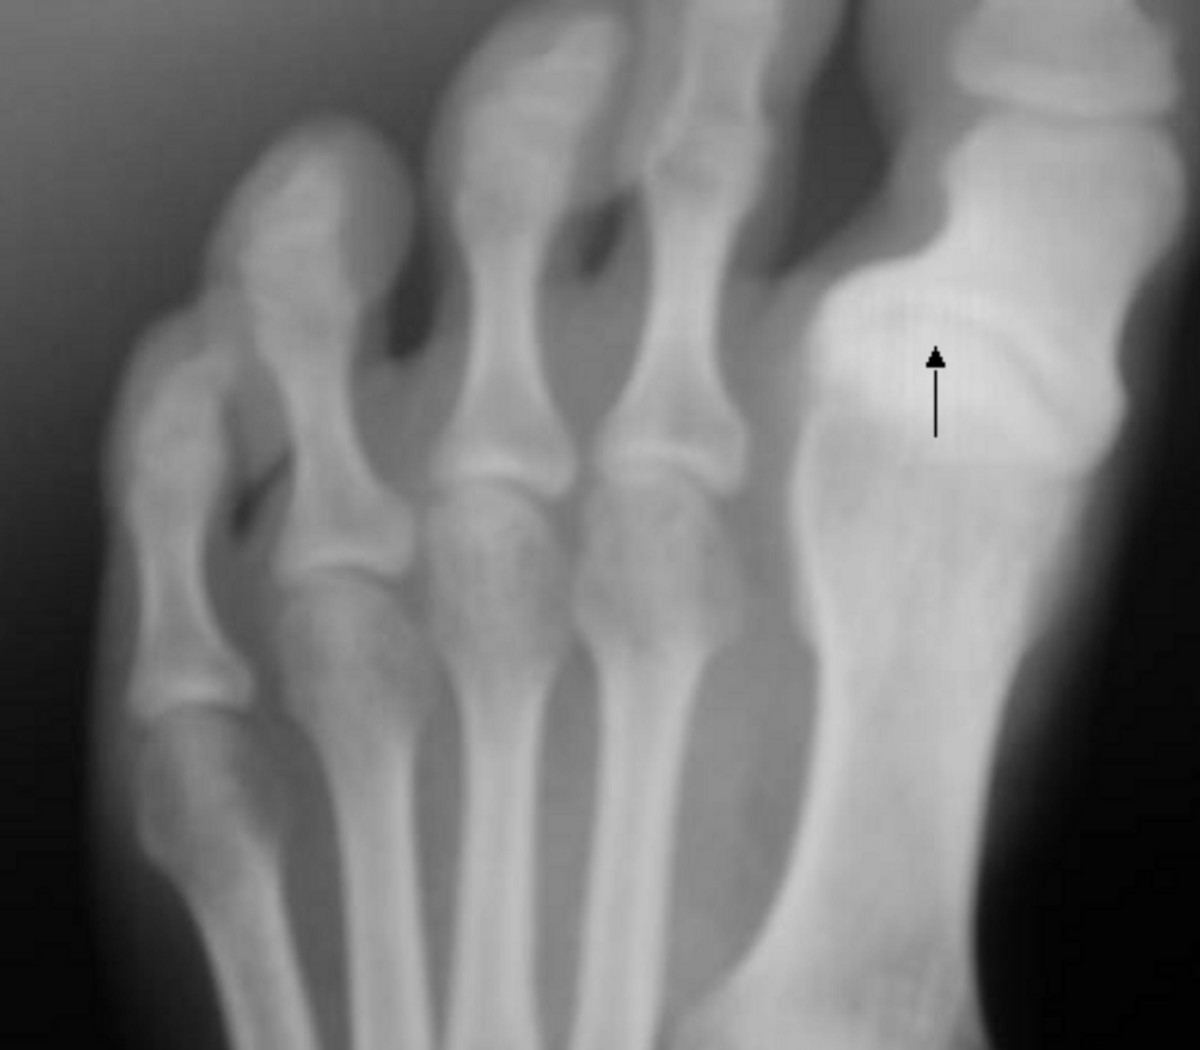

7. Gout

Gout is a form of arthritis caused by the buildup of uric acid crystals in the joints. The National Institute of Arthritis and Musculoskeletal and Skin Diseases (NIAMS) explains that gout attacks often occur suddenly, causing intense pain, redness, and swelling—especially in the big toe.

Gout can be managed through diet, hydration, and prescribed medications that lower uric acid levels. If you experience severe or recurrent episodes, talk to your doctor about long-term management strategies.